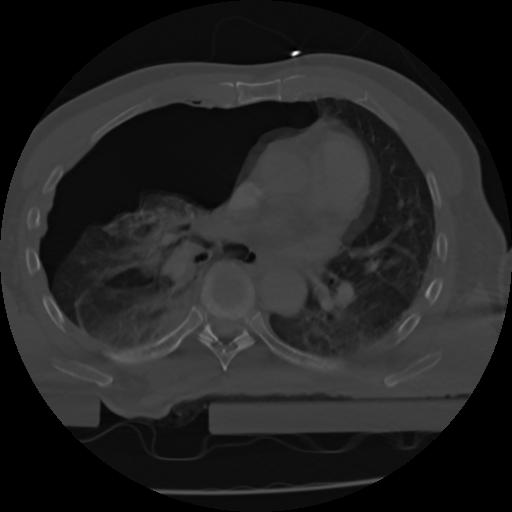

21 ANGIO,CE,Axial,3.0,ANGIO,,